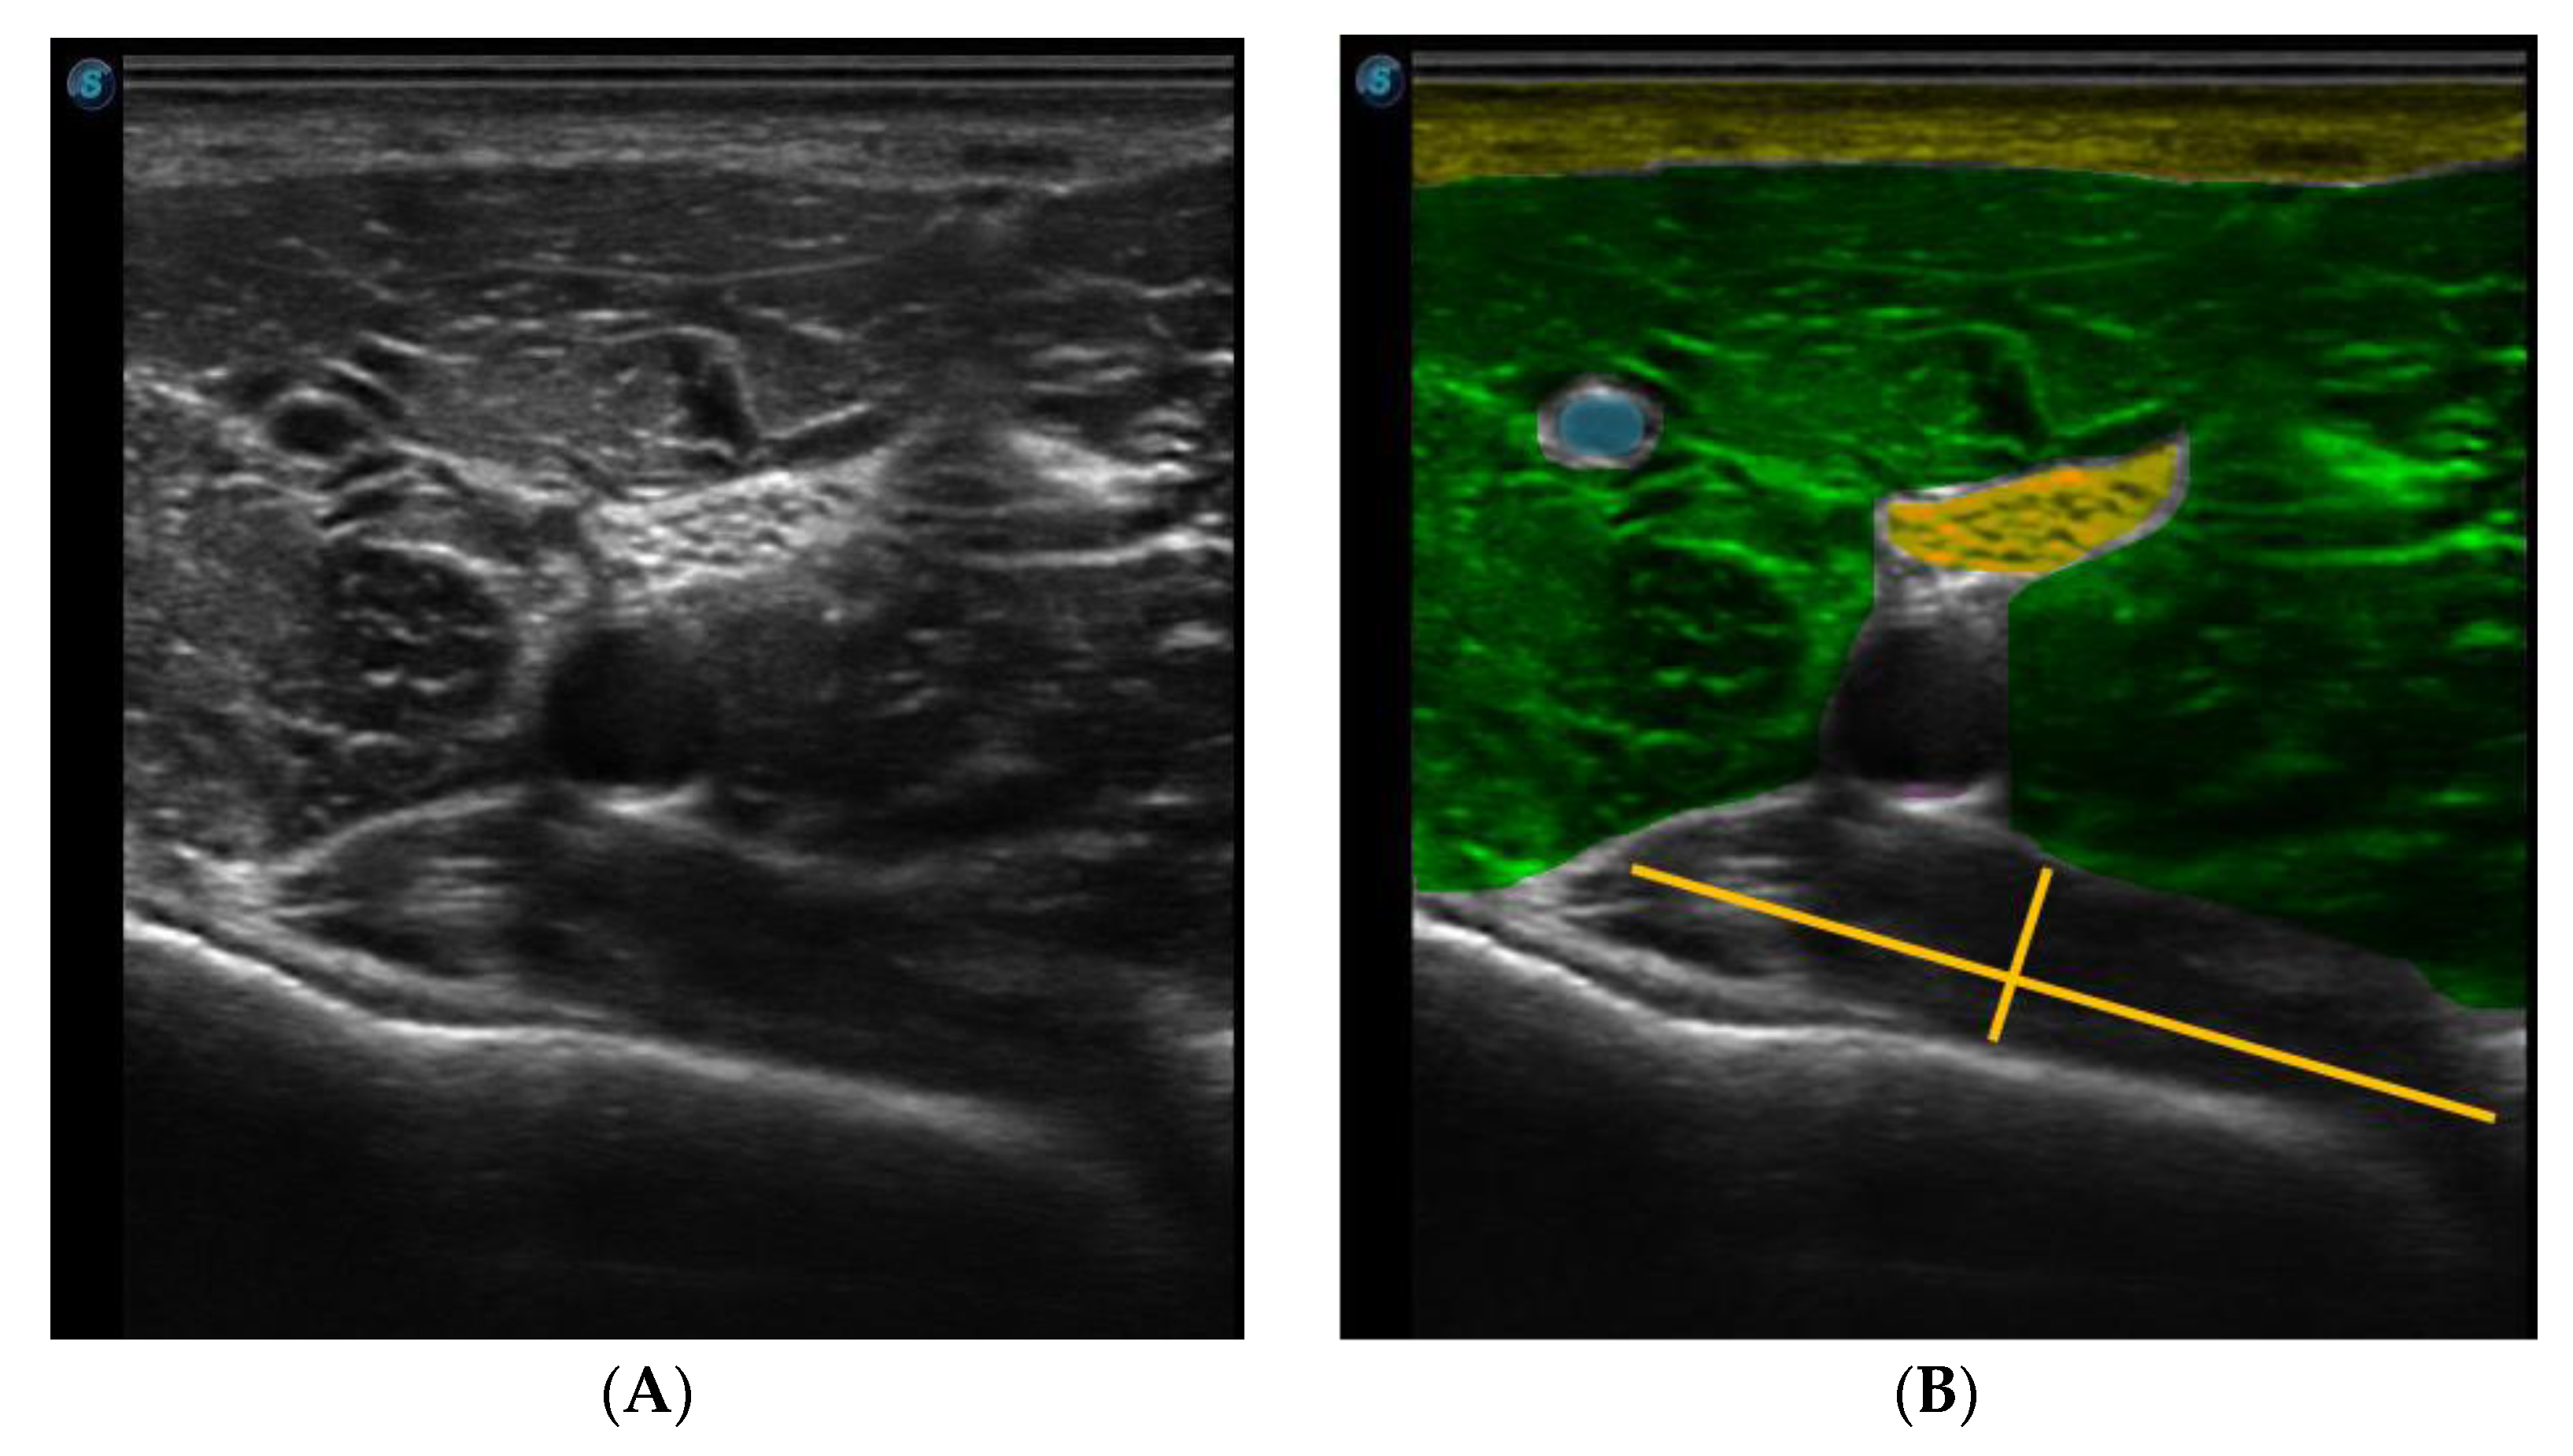

The needle was observed in a long axis, so that the entire length of the needle could be seen in the image. Figure 3 shows the ultrasound image of the popliteus muscle, in the deepest part, just below the vasculonervous bundle.

Figure 3.

Ultrasound image of the popliteal region. (A) Ultrasound B-mode image (B) Colored Ultrasound B-mode image (rose-skin, yellow-fat, green-medialis gastrocnemius, blue-vein, magenta-artery, orange-nerve and red-popliteal muscle).